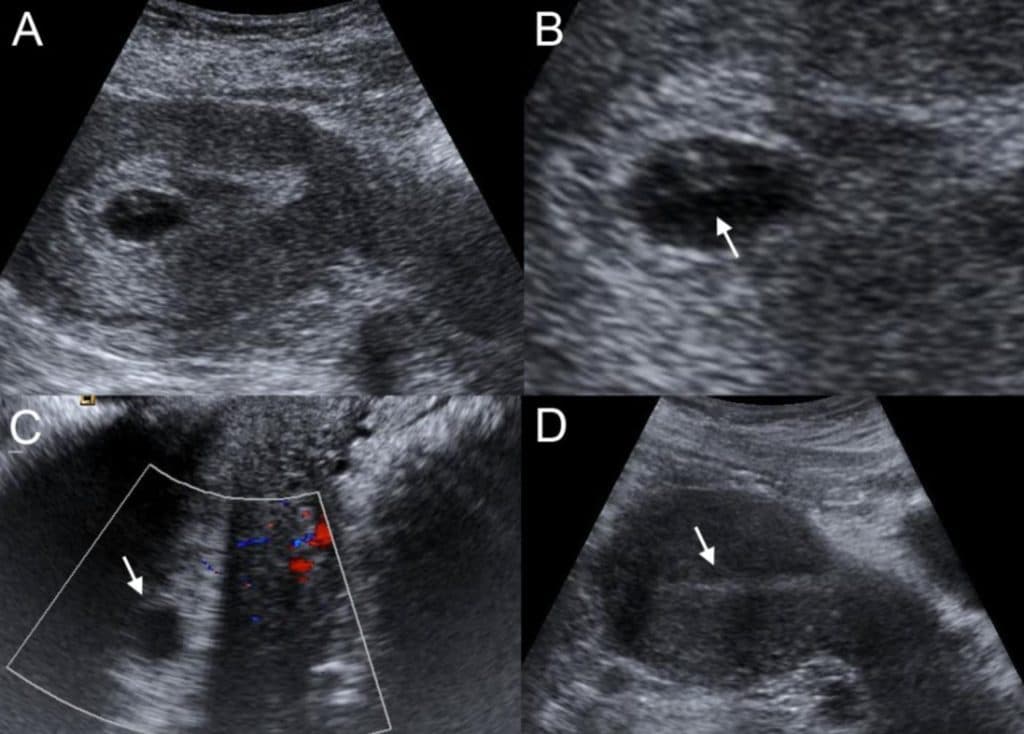

- УЗИ, МРТ, цветное допплеровское картирование;